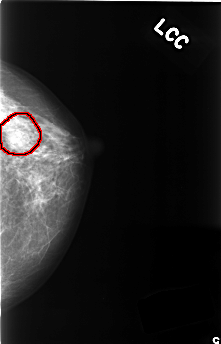

ics_version 1.0 filename C-0385-1 DATE_OF_STUDY 20 5 1996 PATIENT_AGE 40 FILM FILM_TYPE REGULAR DENSITY 2 DATE_DIGITIZED 9 11 1998 DIGITIZER LUMISYS LASER SEQUENCE LEFT_CC LINES 4464 PIXELS_PER_LINE 2872 BITS_PER_PIXEL 12 RESOLUTION 50 OVERLAY LEFT_MLO LINES 4432 PIXELS_PER_LINE 2856 BITS_PER_PIXEL 12 RESOLUTION 50 OVERLAY RIGHT_CC LINES 4560 PIXELS_PER_LINE 2776 BITS_PER_PIXEL 12 RESOLUTION 50 NON_OVERLAY RIGHT_MLO LINES 4576 PIXELS_PER_LINE 2808 BITS_PER_PIXEL 12 RESOLUTION 50 NON_OVERLAY |

FILE: C_0385_1.LEFT_CC.OVERLAY TOTAL_ABNORMALITIES 1 ABNORMALITY 1 LESION_TYPE MASS SHAPE OVAL MARGINS OBSCURED ASSESSMENT 4 SUBTLETY 4 PATHOLOGY BENIGN TOTAL_OUTLINES 1 BOUNDARY |